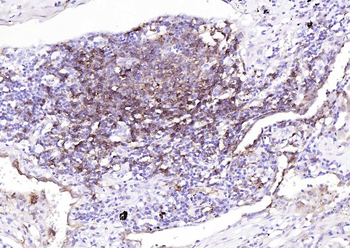

| Tested applications | IHC |

| Dilution range | Immunohistochemistry (Frozen & Formalin-fixed) (1-2ug/ml for 30 minutes at RT),(Staining of formalin-fixed tissues is enhanced by boiling tissue sections in 10mM Citrate Buffer, pH 6.0, for 10-20 min followed by cooling at RT for 20 minutes),Optimal dilution for a specific application should be determined. |

| Application notes | Positive Control: Human tonsil or lymph node |